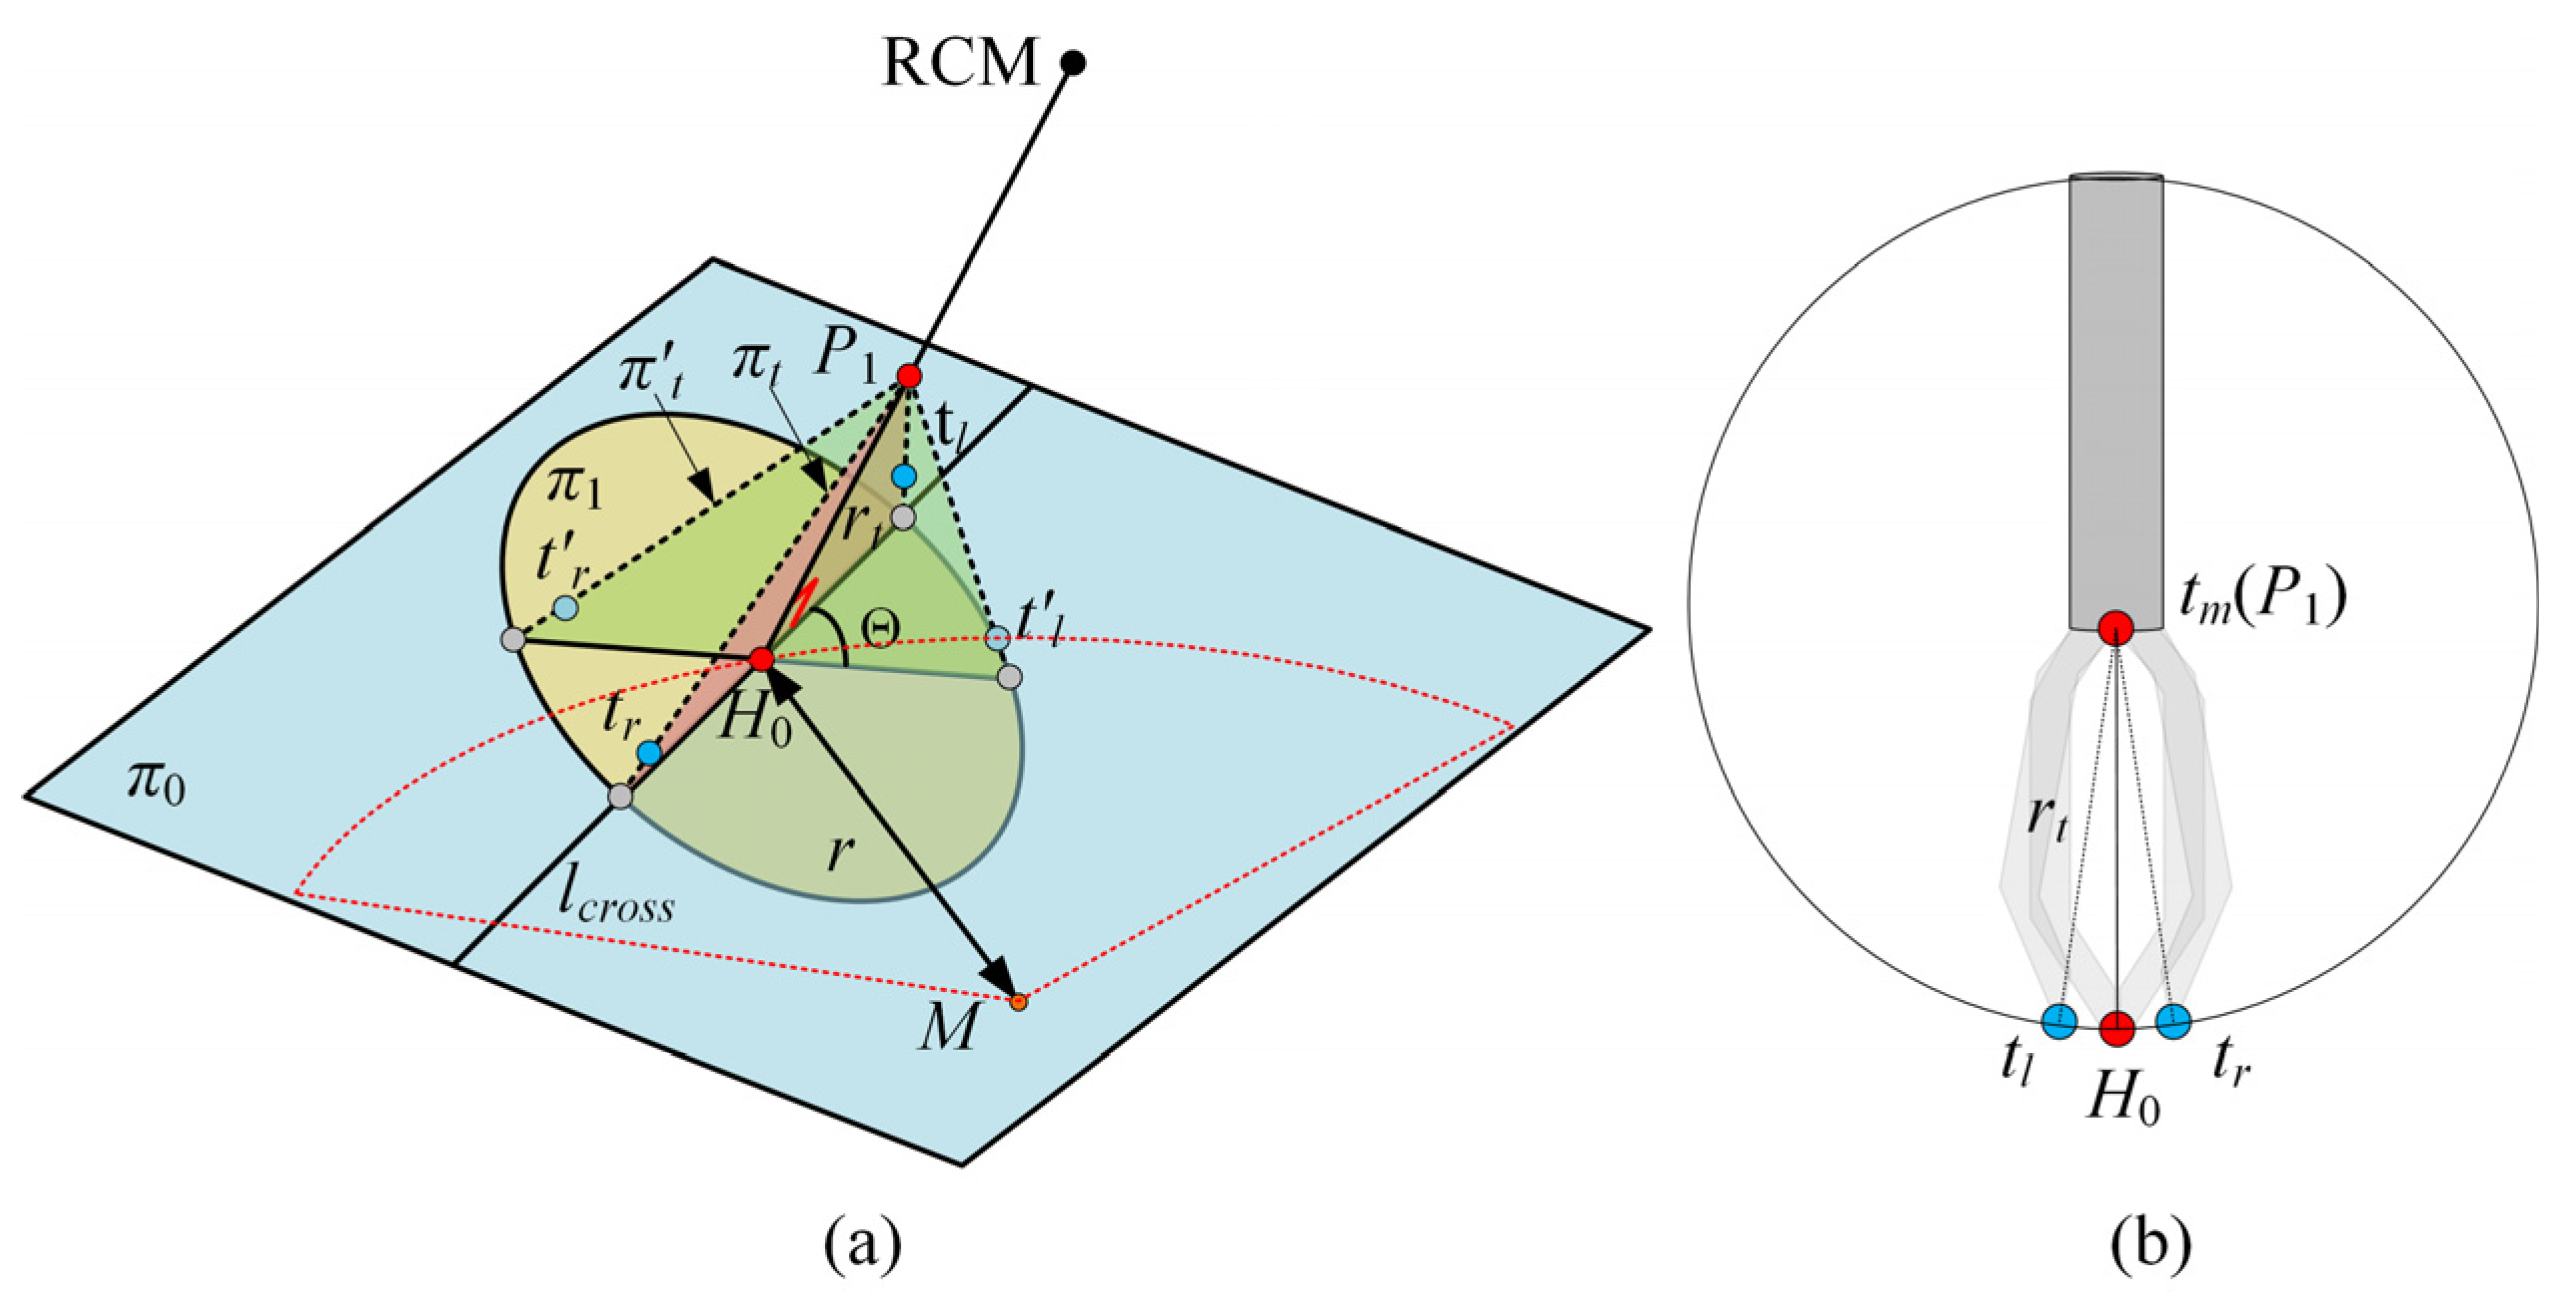

2.4. Automatic Surgical Trajectory Planning Method